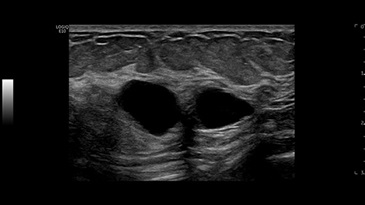

Кисты в молочной железе, ML6-15-D